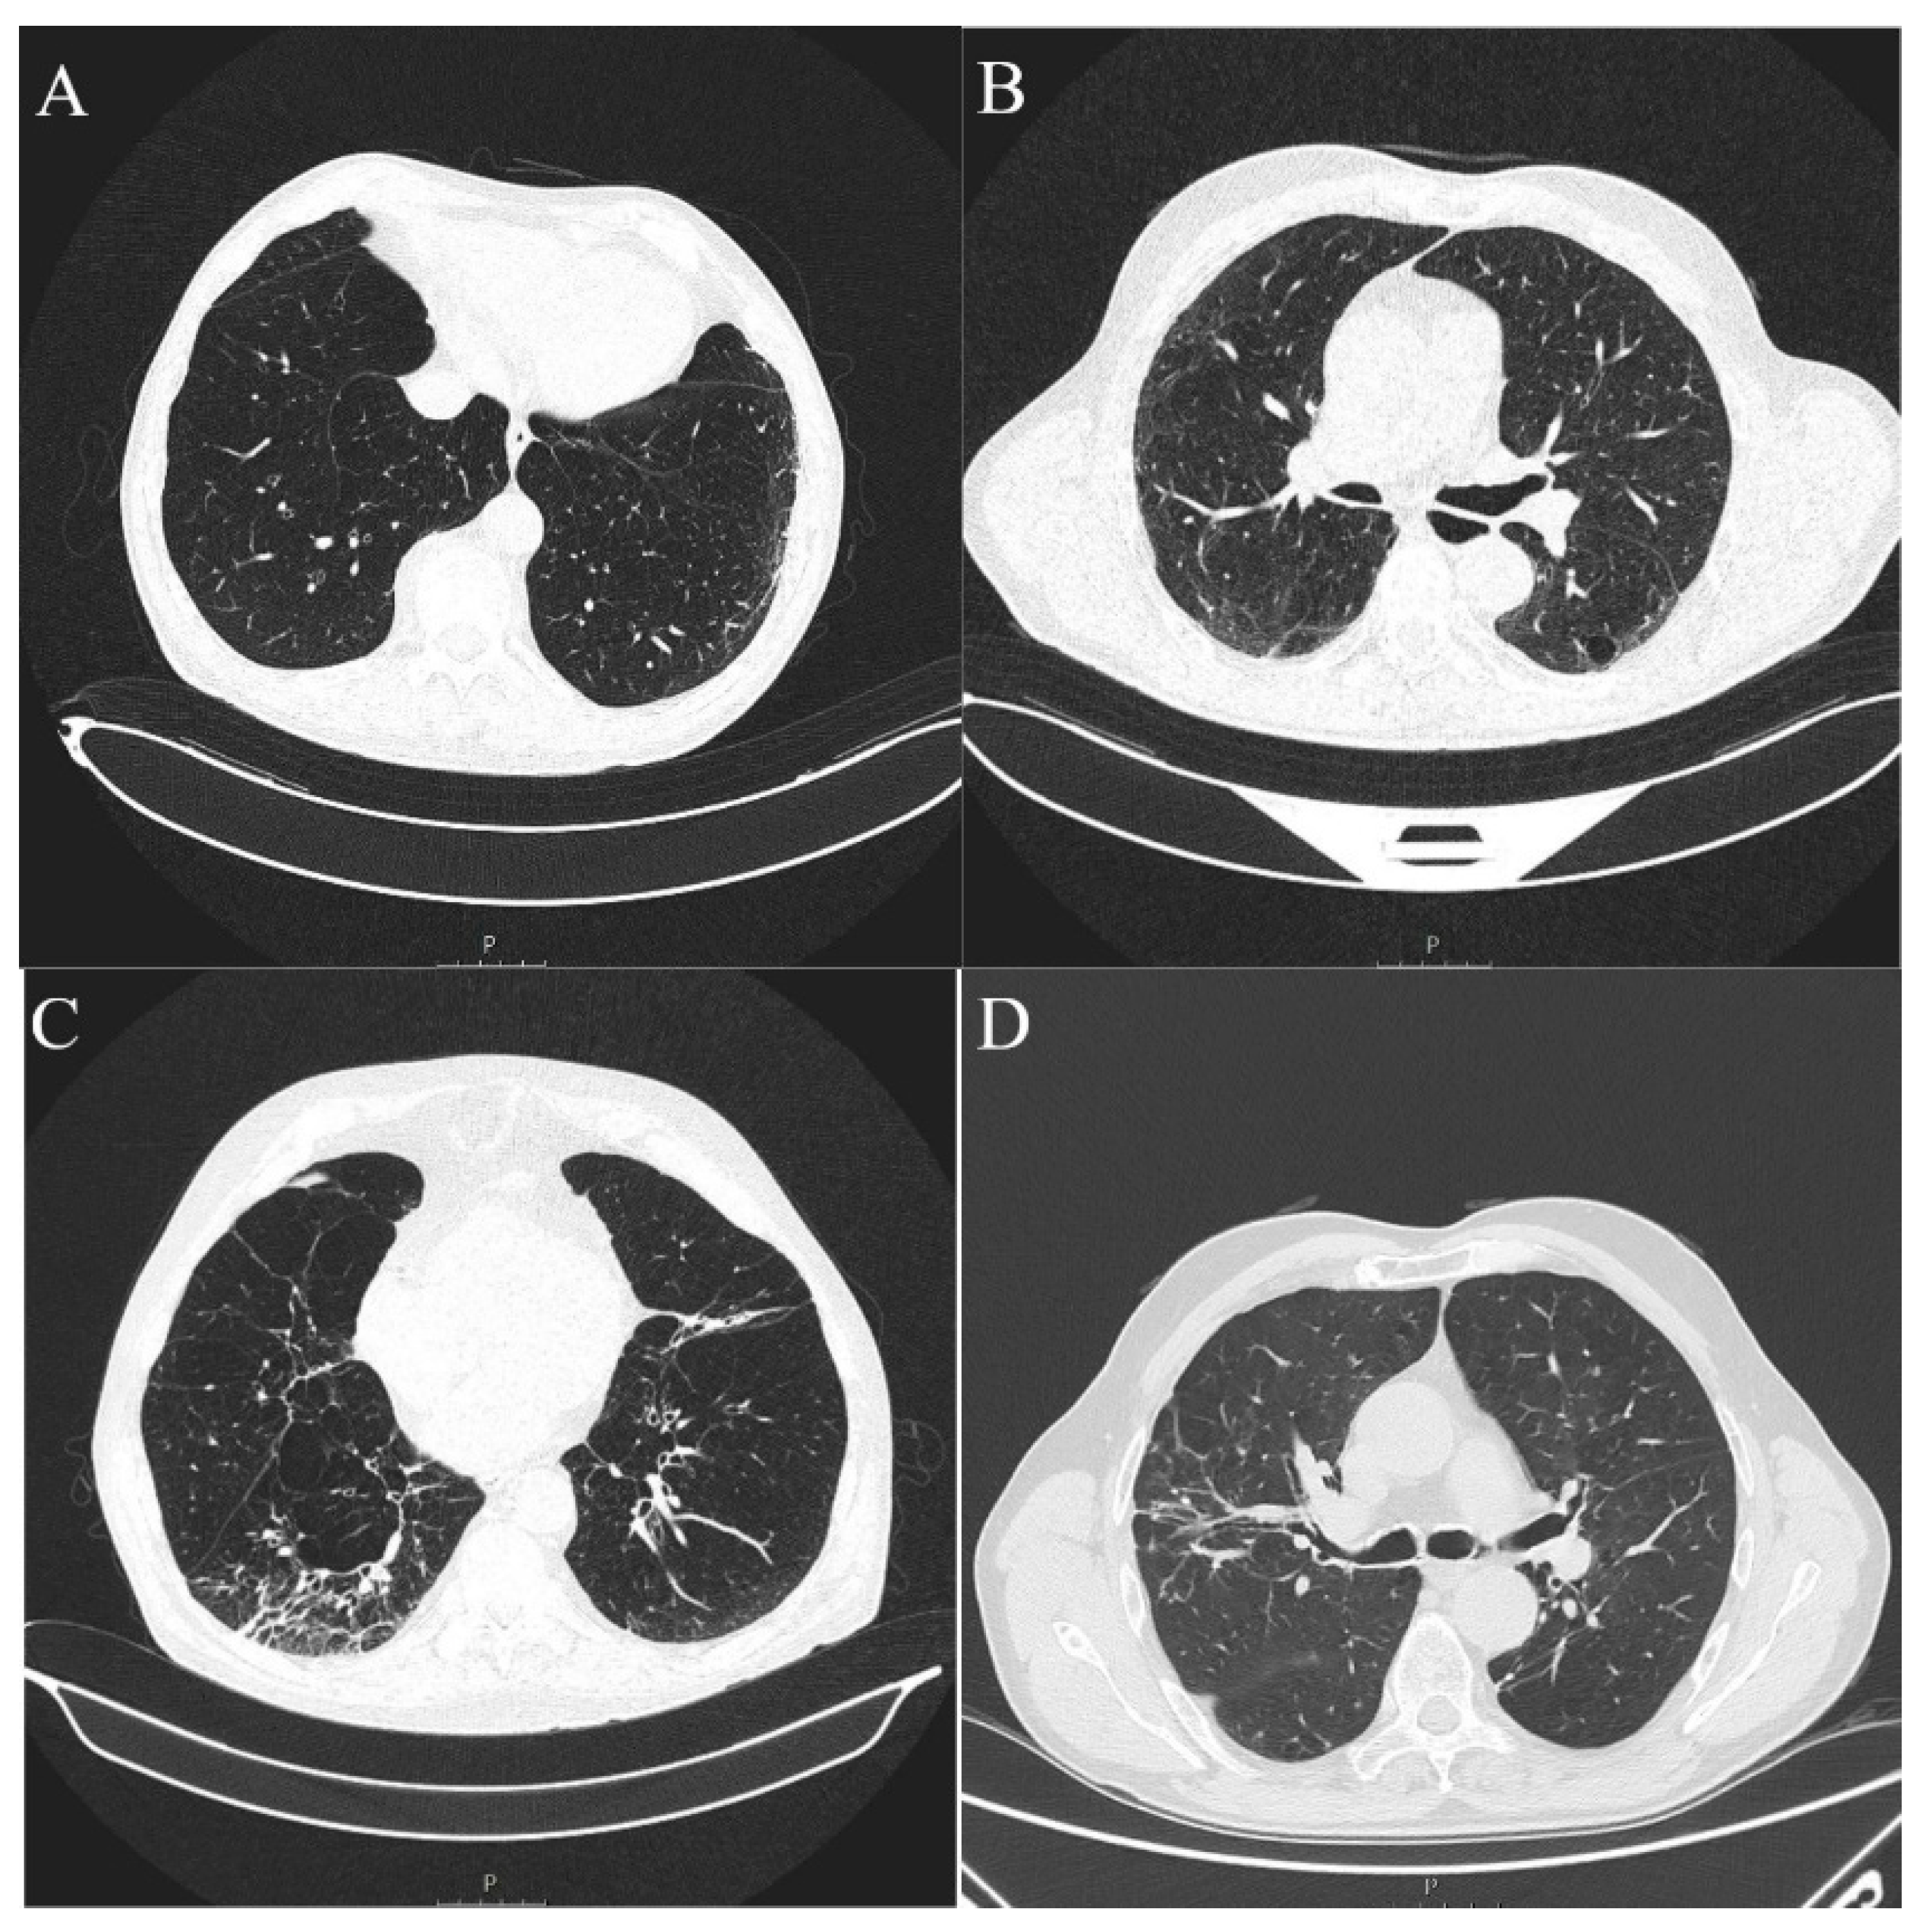

ILA changes were most prevalent in the lower lung zones (n = 11, 73.3%), followed by upper zones (n = 6, 40.00%) and least reported in the middle lung zones (n = 2, 13.3%), which was significantly different (p = 0.0045). The most commonly reported ILA subtype was subpleural non-fibrotic (n = 9, 60%), followed by subpleural fibrotic (n = 4, 26.67%) and non-subpleural (n = 2, 13.33%) (p = 0.0354) (Table 3, Figure 3 and Figure 4). Reticulations were the most frequently described pattern in almost every patient with ILA changes (n = 14, 93.3%) (p < 0.0001). Other ILA patterns were non-emphysematous cysts (n = 8, 53.33%), distortion with traction bronchiectasis (n = 6, 40.00%) and ground glass opacity in four (26.67%) patients. Distortion with honeycombing was not reported in any of the patients (Table 4, Figure 3 and Figure 4).

Figure 4.

Axial MSCT scans of pretreatment lung parenchyma demonstrating typical ILA findings in HNSCC patients (A). Unilateral subpleural non-fibrotic type characterized by subpleural reticulations surrounded by areas of GGO (B). Bilateral subpleural non-fibrotic changes manifesting as subpleural reticulations surrounded by areas of GGO and sporadic non-emphysematous cysts (C). Unilateral subpleural fibrotic changes in the right lung, manifesting as traction bronchiectasis and bronchiolectasis with parenchymal distortion and zones of GGO. Contralateral lung shows mild traction bronchiectasis and subpleural reticulations (D). Unilateral non-subpleural, traction bronchiectasis with architectural distortion surrounded by small zones of GGO. Two small intraparenchymal calcifications in close proximity were not classified as ILA.